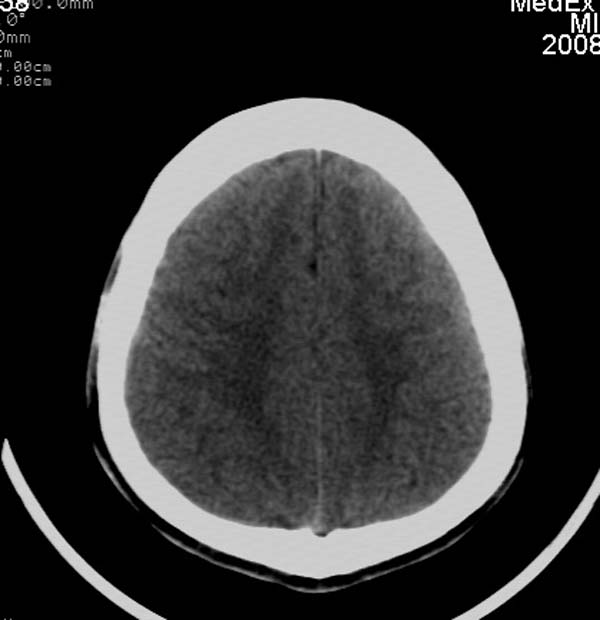

患者,男,24岁。头面部外伤后意识障碍1小时。

小脑幕缘密度增高,考虑有少量出血,建议复查

考虑右侧天幕缘少量蛛网膜下腔出血;建议:必要时复查。

支持少量蛛网膜下腔出血,建议复查.

1)考虑少量蛛网膜下腔出血;建议:必要时复查。2)桥前池及左侧环池表皮样囊肿可能。建议:行mri检查。

当ct表现不明显,临床症状相当明显时,建议mri+dwi序列除外弥漫性轴索损伤之可能。